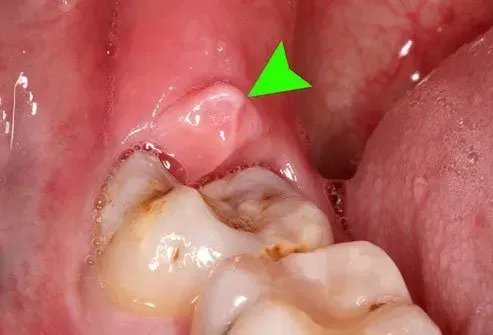

Péricoronite

Lorsqu'une dent de sagesse éclate - même en partie - elle peut être vulnérable à la péricoronite. C'est le nom de la douleur et de l'infection des gencives trouvées dans 6% à 10% des dents de sagesse érutées. Habituellement, lorsque les dents de sagesse éclatent naturellement, ce n'est pas un problème. Il a tendance à survenir dans des dents qui ont émergé de la ligne des gencives très lentement - généralement la dent de sagesse inférieure.

Péricoronite can be either acute or chronic. Acute cases cause severe pain that often radiates into nearby areas in the mouth. It can lead to gum swelling tightness in the jaw swollen lymph nodes difficulty swallowing and difficulty falling asleep. Chronic cases provoke dull pain that can go away for months and can leave a bad taste in your mouth. Sometimes exhaustion and pregnancy can cause chronic pericoronitis pain to reoccur.

Des études montrent que 35% à 43% des patients atteints de péricoronite ont récemment souffert d'une infection respiratoire suggérant que ces infections peuvent contribuer à ce problème de santé bucco-dentaire. Le stress peut les rendre plus probables aussi. C'est aussi plus courant chez les femmes que chez les hommes.